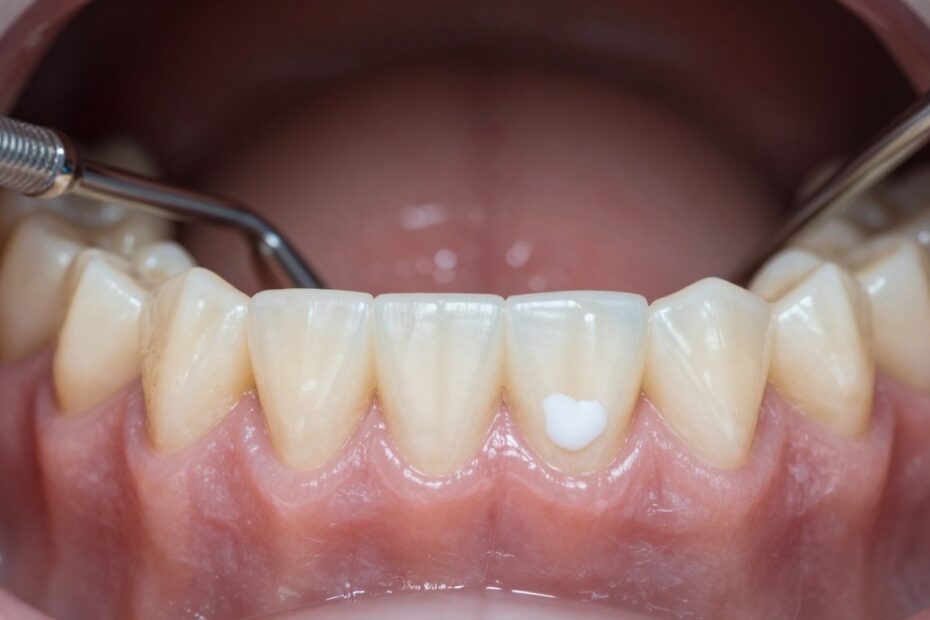

Kiedy biała zmiana nie schodzi po przetarciu, może to być objaw leukoplakii. Kliniczna definicja to: biała zmiana w obrębie błony śluzowej, której nie da się zetrzeć i której nie wyjaśnia inna jednostka chorobowa.

Leukoplakia może występować jako gładkie plamy, smugi, siateczka, pęknięcia lub obraz przypominający mozaikę. Zmiany lokalizują się m.in. na policzkach, krawędziach języka, dziąsłach i wargach.

Wyróżnia się postać homogenną i niehomogenną. Homogenna jest zwykle gładka i mniej niepokojąca. Niehomogenna ma czerwone pola, nadżerki lub guzki i niesie większe ryzyko dysplazji lub raka.

Podejrzenie rośnie, gdy zmiana jest utrwalona, nawracająca lub powiększająca się. Nie próbuj samodzielnie „leczyć” takiej zmiany domowymi metodami — zorganizuj ocenę stomatologiczną.